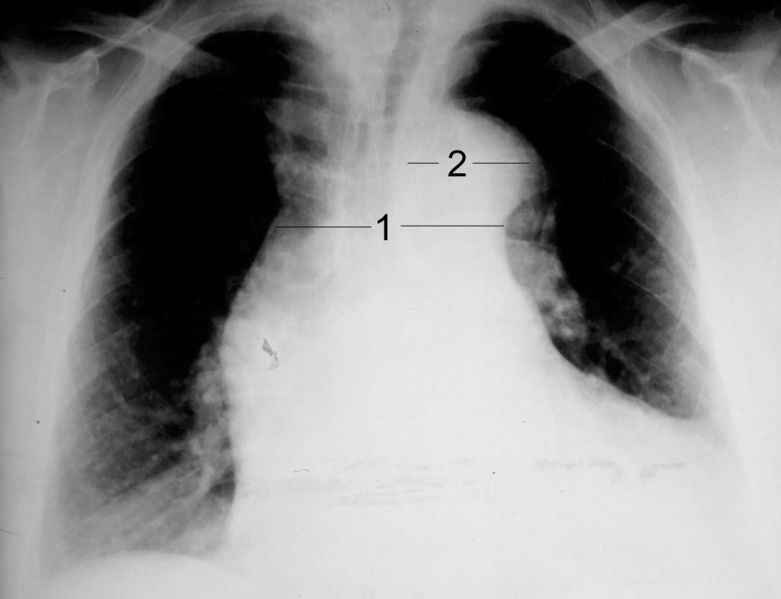

CXR showing widened mediastinum and porminent aortic knob

| current | 17:43, 19 May 2016 | 2,052 × 1,575 (291 KB) | Alvarez13 (talk | contribs) | CXR showing widened mediastinum and porminent aortic knob |